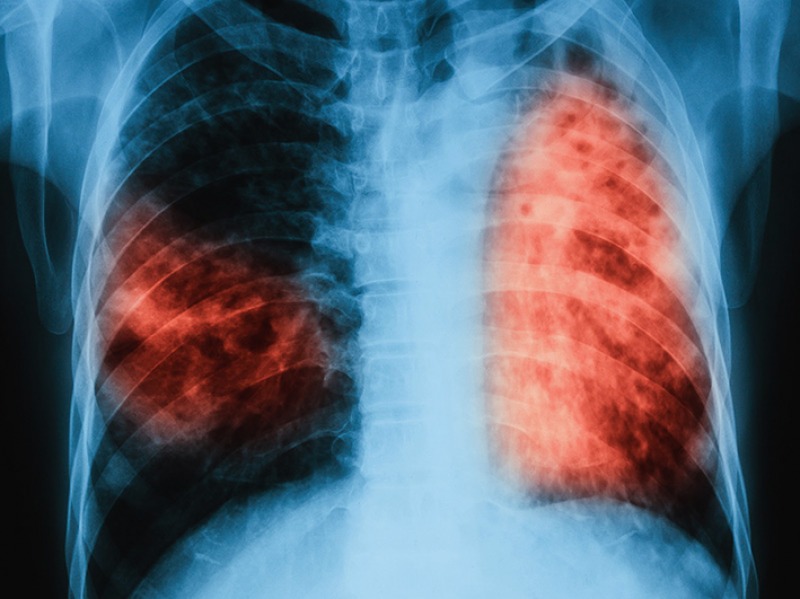

Es una enfermedad bacteriana infecciosa grave que afecta principalmente a los pulmones aunque también puede dañar otras partes del cuerpo como los riñones, columna vertebral y el cerebro.

Hay diferentes síntomas de la tuberculosis, dependiendo del área del cuerpo en donde las bacterias se estén multiplicando. Cuando se da en los pulmones, estos son los síntomas más recurrentes: